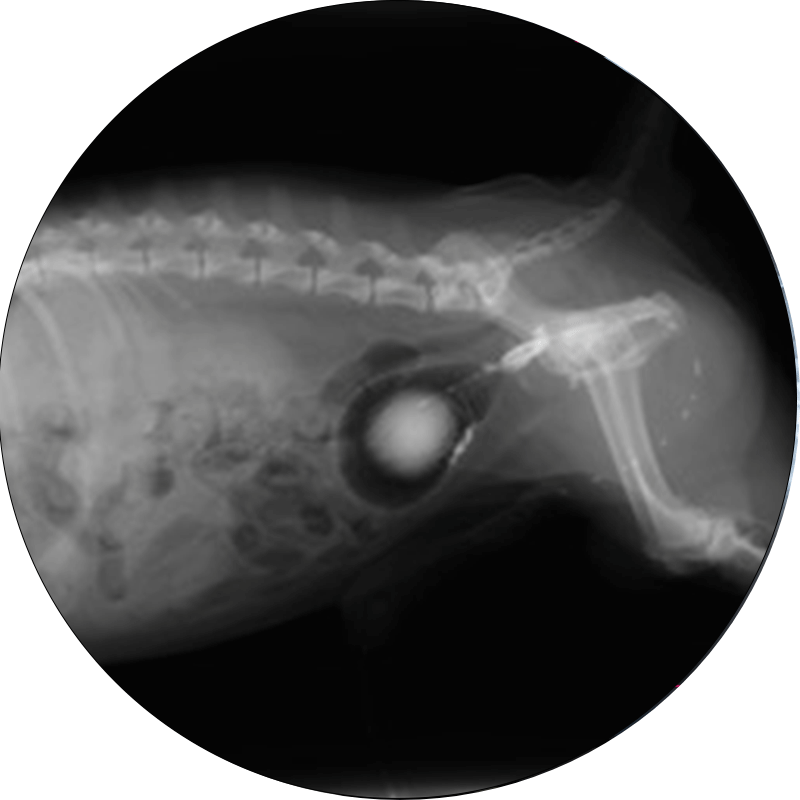

エックス線検査

腎臓、尿路、膀胱、前立腺、子宮などの異常を評価するために使用されます。エックス線検査は、腎臓や尿路の構造的な異常や、結石、腫瘍の有無を確認するために非常に有効な診断手段で、一般的に腹部全体または網羅的に評価することが可能です。また、必要に応じて造影剤を使用することでさらに腎臓の詳細な評価が可能です。腹部超音波と併せて実施されることが多いです。